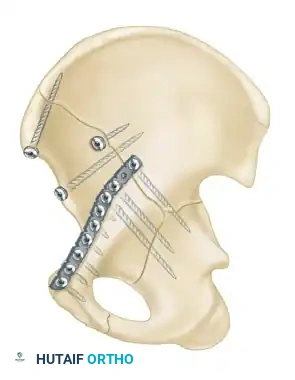

- Both-Column Fractures: The most complex pattern. All articular segments are detached from the intact posterior ilium (which remains attached to the sacrum).

Clinical Pearl: The Spur Sign

In a both-column fracture, the intact portion of the ilium (attached to the sacroiliac joint) projects laterally relative to the medially displaced, fractured acetabular columns. On an obturator oblique radiograph, this intact bone appears as a sharp spike, known as the "Spur Sign." Its presence is pathognomonic for a both-column fracture.